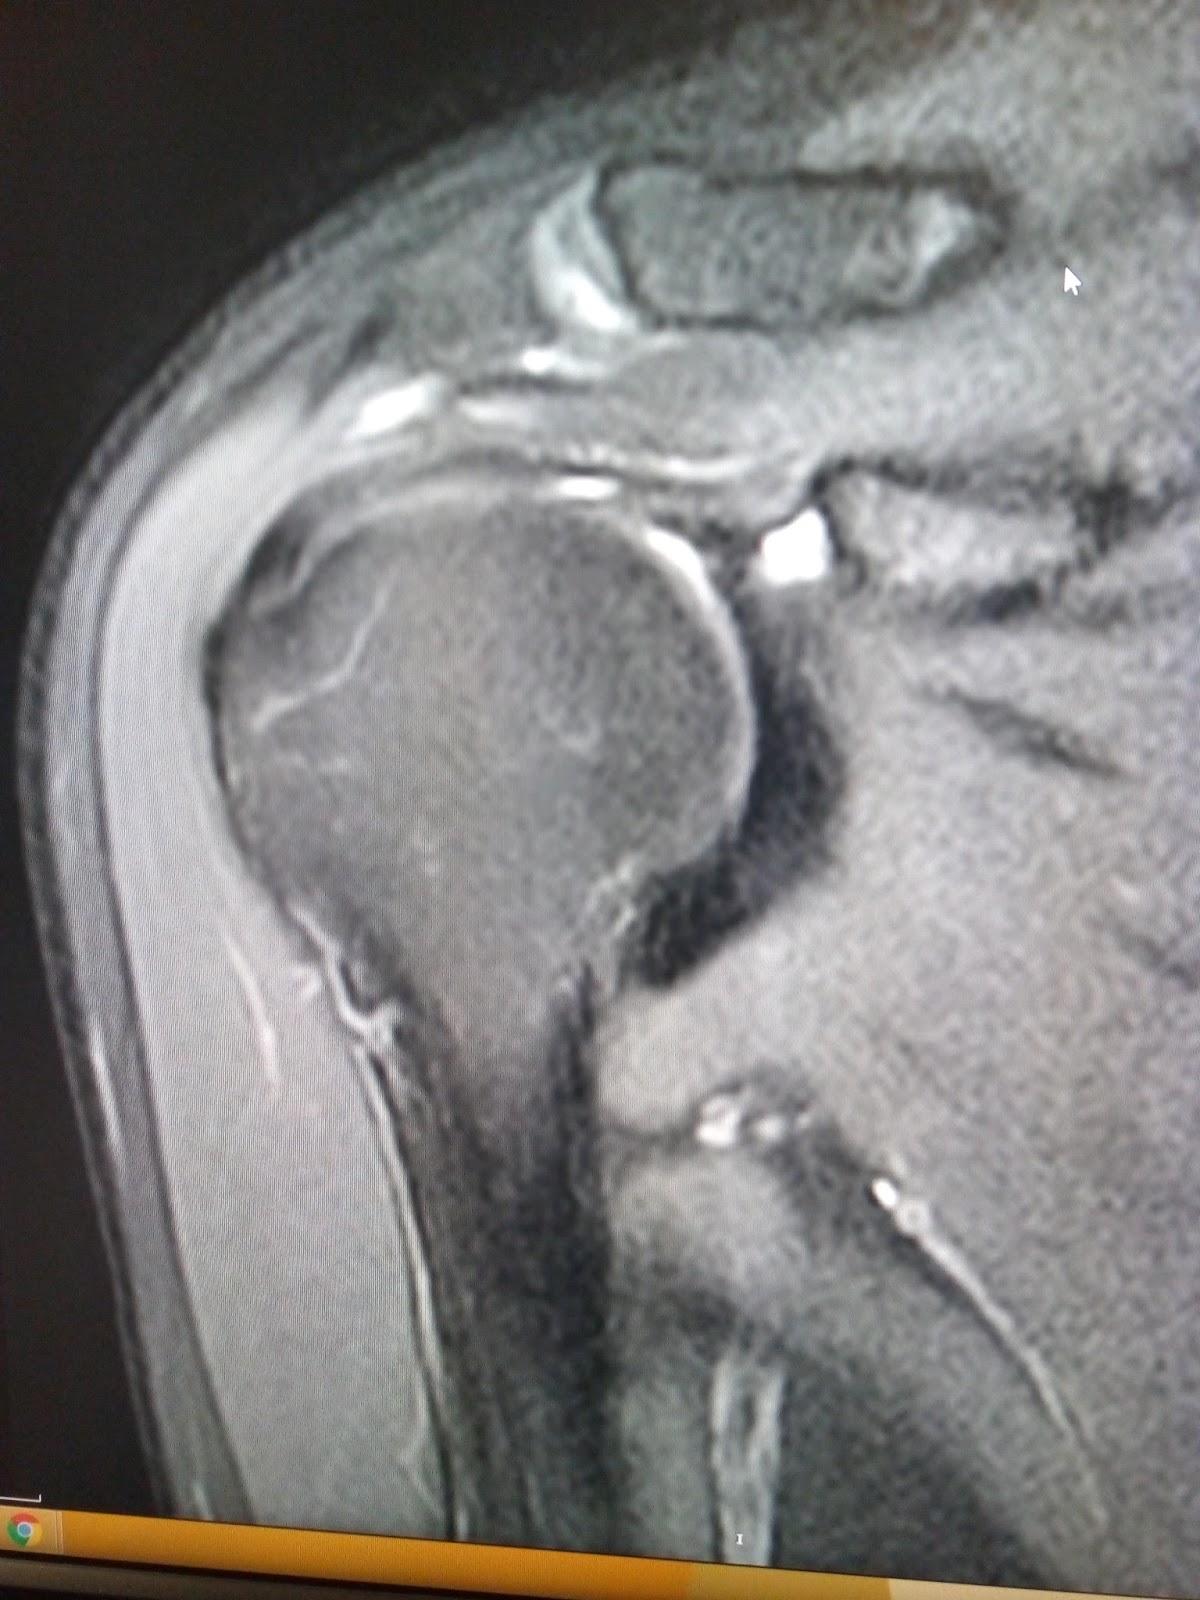

from www.indianradiology.com

Adhesive capsulitisMRI Sumer's Radiology Blog

From sumerdoc.blogspot.com

Adhesive capsulitisMRI Sumer's Radiology Blog Define Adhesive Capsulitis adhesive capsulitis, also known as “frozen shoulder,” is a common shoulder condition characterized by pain and decreased range of motion, especially in external rotation. adhesive capsulitis is a chronic fibrosing condition characterized by insidious and progressive severe restriction of both. frozen shoulder is also referred to as adhesive capsulitis, painful stiff shoulder, and periarthritis. frozen shoulder. Define Adhesive Capsulitis.

Adhesive capsulitisMRI Sumer's Radiology Blog Define Adhesive Capsulitis the hallmark sign of frozen shoulder, also known as adhesive capsulitis, is the inability to move your shoulder—either on your own or with the help of someone. frozen shoulder is also referred to as adhesive capsulitis, painful stiff shoulder, and periarthritis. adhesive capsulitis, also known as “frozen shoulder,” is a common shoulder condition characterized by pain and. Define Adhesive Capsulitis.